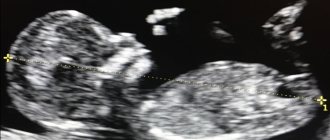

Гиперэхогенный фокус в левом желудочке сердца плода

Феномен «гольфного мяча»

Вы пришли на второй скрининг, а Вам говорят, что у ребенка в левом желудочке гиперэхогенный фокус. «Гиперэхогенный» означает то, что на фоне тканей сердца участок обладает повышенной яркостью (плотностью). Феномен «гольфного мяча» возник по той причине, что такое гиперэхогенное включение по форме напоминает мяч, которым играют в гольф, и при сердечных сокращениях подпрыгивает cловно мячик. Чаще всего гиперэхогенный фокус (ГЭФ) обнаруживается в левом желудочке (ЛЖ), реже — в правом желудочке (ПЖ) и других камерах сердца. До сих пор остается загадкой, почему такой гиперэхогенный фокус (ГЭФ) в сердечной мышце, имеющий плотность костной ткани, бесследно исчезает после рождения.